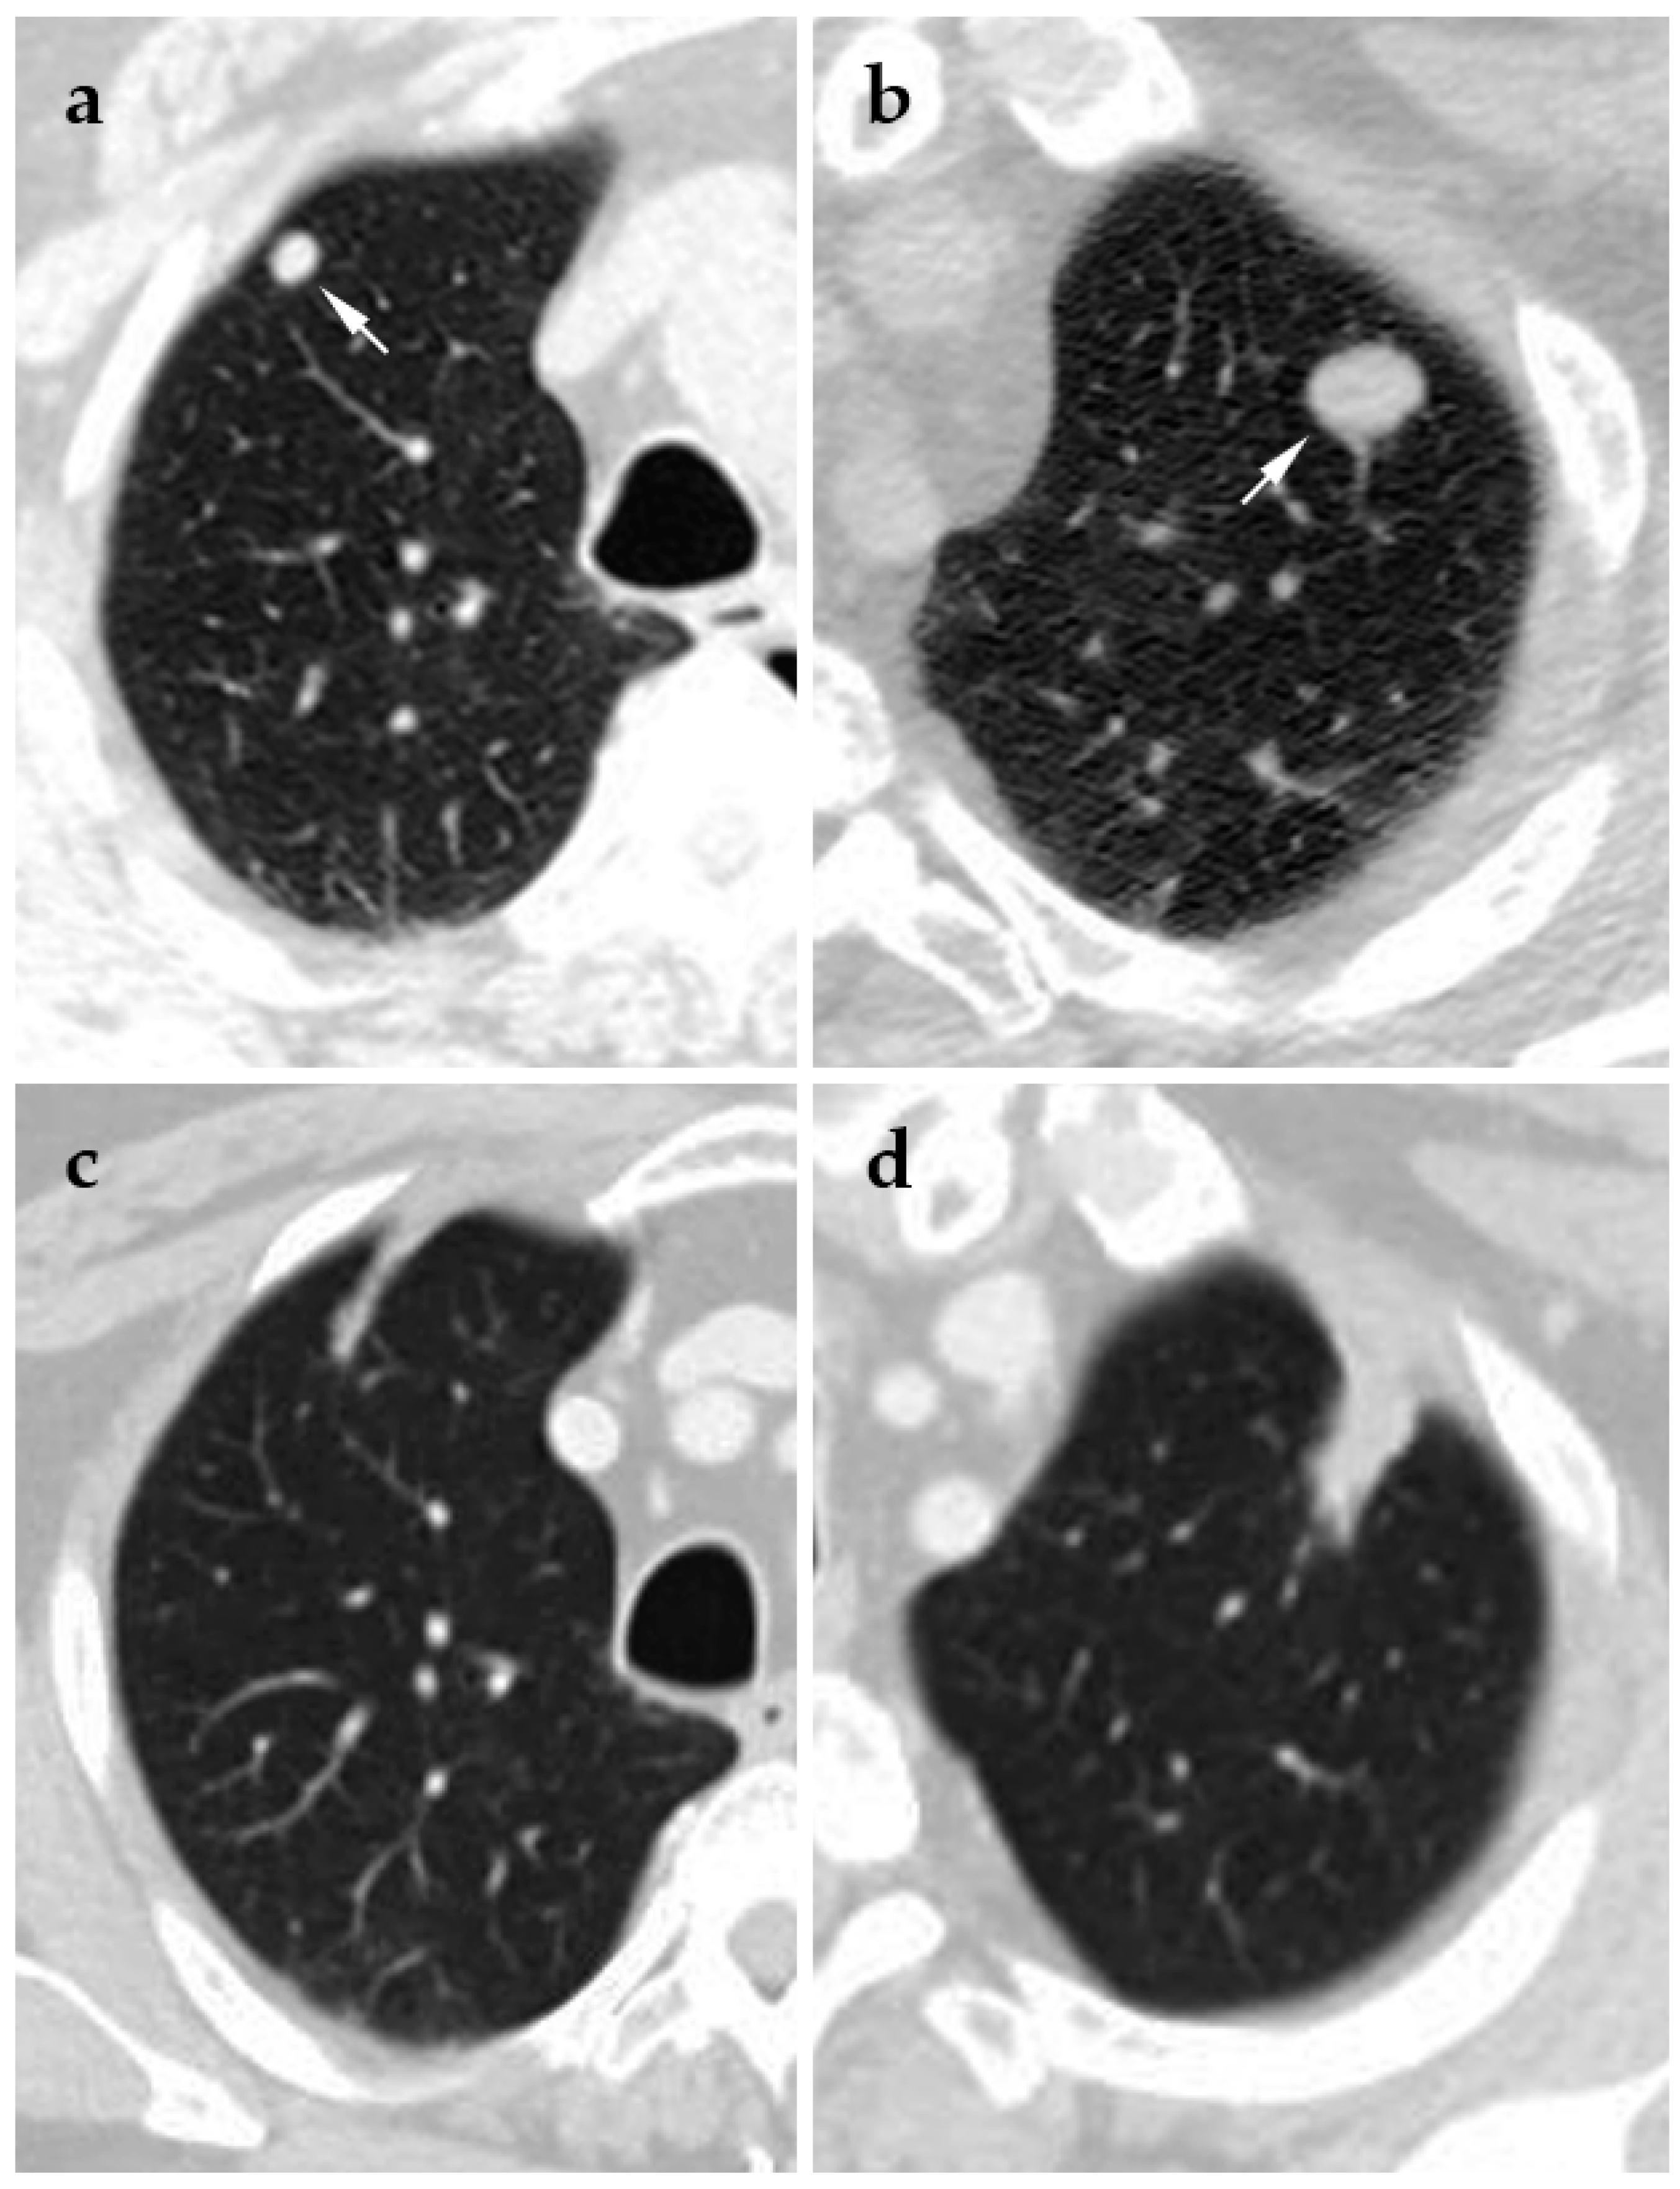

4.1. Cryoablation

- Chheang, S.; Abtin, F.; Guteirrez, A.; Genshaft, S.; Suh, R. Imaging features following thermal ablation of lung malignancies. Semin. Intervent. Radiol. 2013, 30, 157–168. [Google Scholar] [CrossRef] [PubMed]